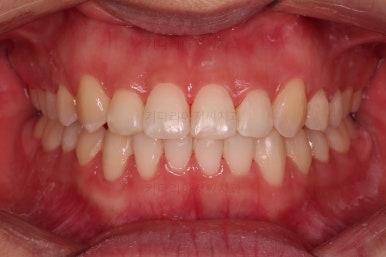

치료가 1년만에 종료가 되었네요.

치아가 가지런해졌고, 교합이 잘 맞는 모습이에요.

부산교정 전후사진을 비교해 볼게요.

치열의 모습이 좋아졌고, 웃을 때 보이는 치열이 가지런해서 미소도 훨씬 예뻐졌네요.

옆라인이라던지 입을 다물었을 때의 느낌은 원래도 좋으셨기 때문에 거의 그대로 유지가 되었고요.

1년정도 만의 만족스러운 치료였습니다.

이상 비발치로 덧니와 삐뚤한 앞니를 교정치료한 치료사례였습니다.